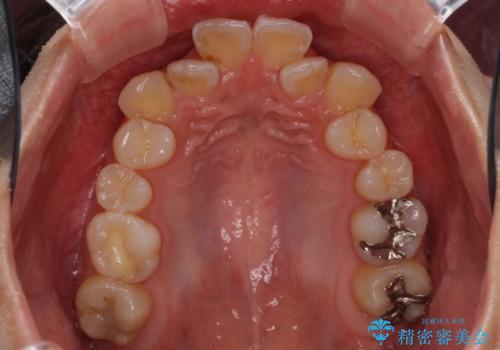

- 上下前歯のデコボコと、それによる磨きづらさを気にして来院された患者様です。

叢生解消のため、上下左右第一小臼歯4本を抜歯し、ワイヤー装置にて矯正治療を行うこととしました。